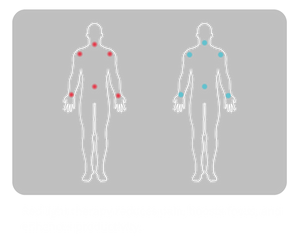

Benefits with Red Light

Every Body Part

penetration therapy. By mimicking natural light, red light therapy offers a safe, gentle alternative to pharmaceuticals

and invasive procedures, providing you with an effective solution for pain management, and overall wellness.